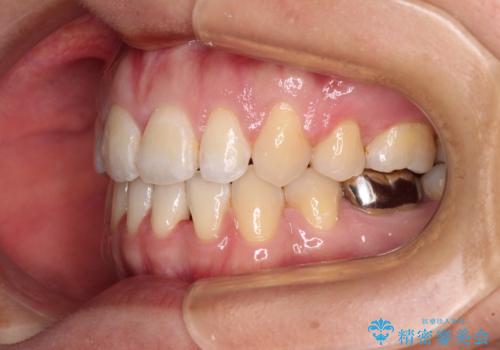

- 唇の閉じにくさを気にして来院された患者様です。

上下左右第一小臼歯4本を抜歯し、ワイヤー装置にて口元を引っ込めるよう矯正治療を行うこととしました。

骨格的に下顎がやや前方にあるため、横顔のシルエットが著しく変化することはありませんでしたが、口元はスッキリと引っ込み、唇が閉じやすくなりました。